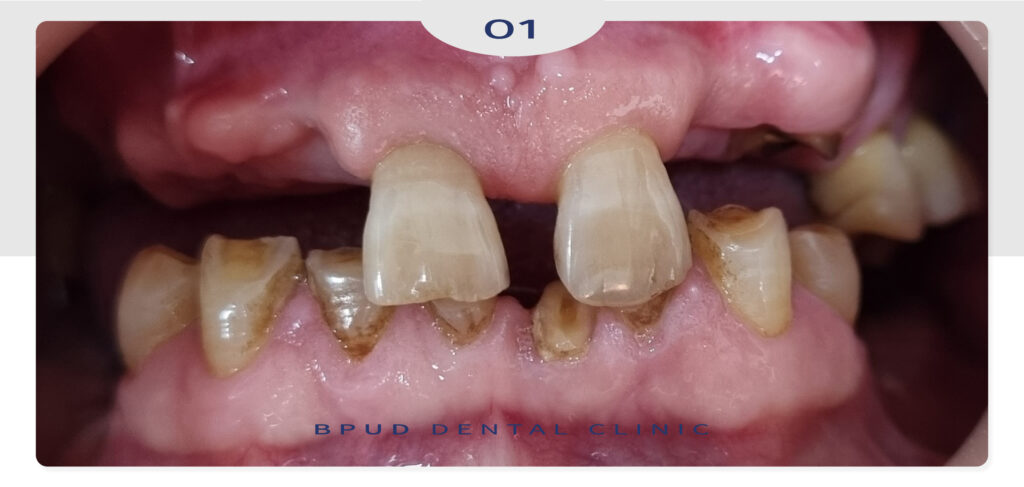

최종 보철물까지 문제 없이

마무리된 모습인데요.

환자분께서도 심미적으로 매우 만족하셨고

양쪽으로 식사가 가능하시다며 감사함을

전해주셨습니다.

또한, 시간이 없어서 치료를 잘 못받으셨는데

하루에 수술을 끝낼 수 있는 점이 너무

좋았다는 말씀을 해주셨습니다.